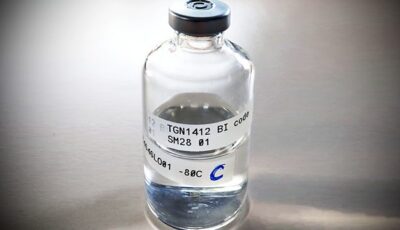

The Drug Trial: Emergency at the Hospital

The Drug Trial: Emergency at the Hospital

Documentary telling the story of one of the most infamous medical emergencies in recent British history, when six healthy men took ...